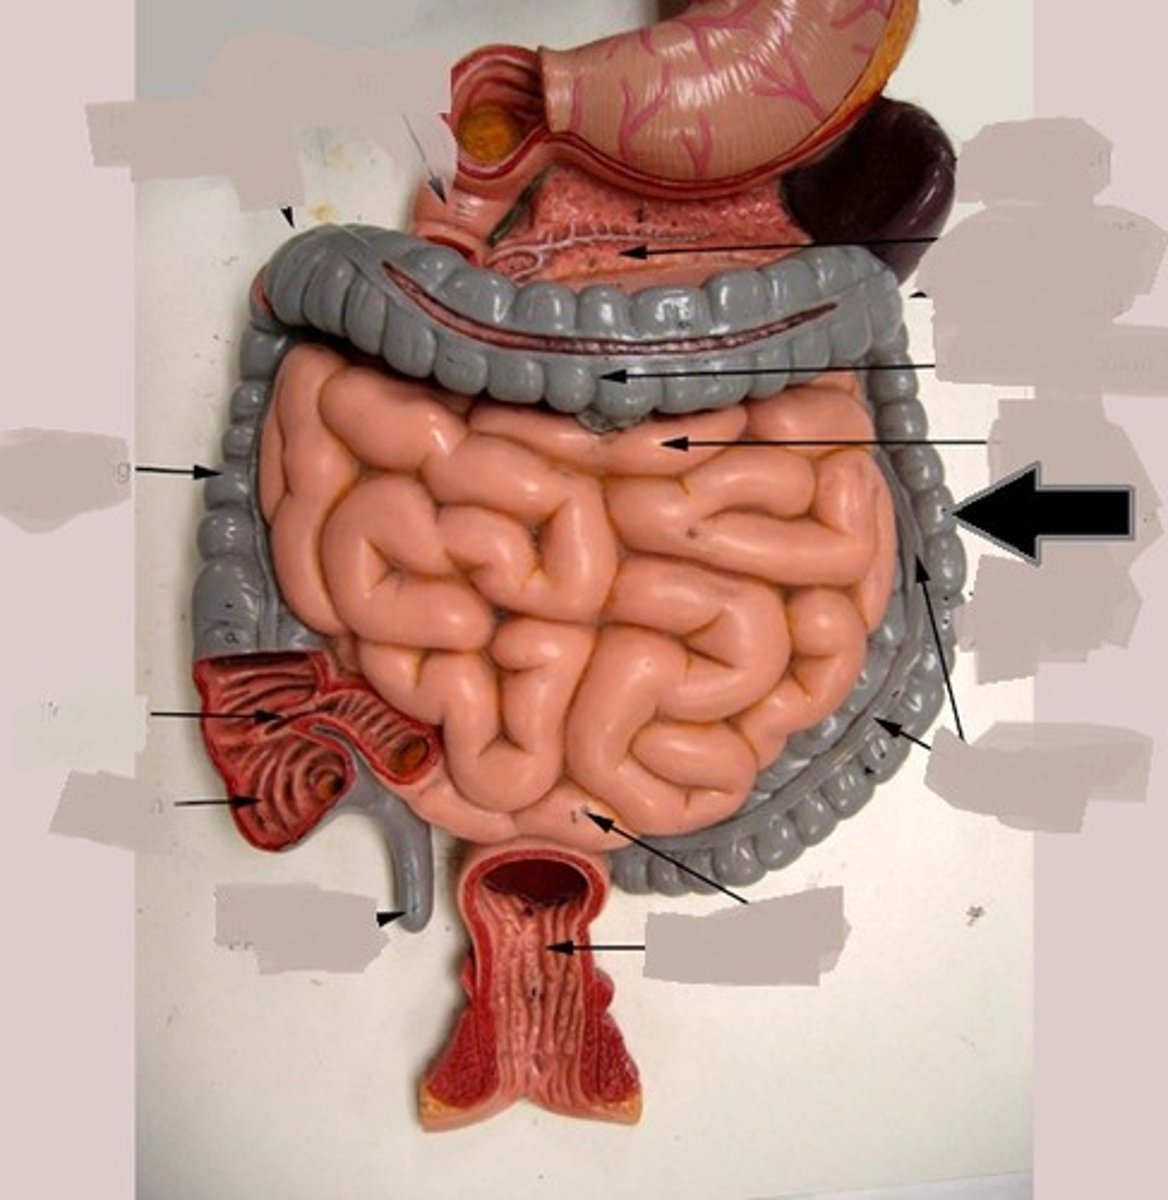

large intestine

cecum

Specific

cecum

ascending colon

Specific

transverse colon

Specific

descending colon

Specific

sigmoid colon

specific

illeocecal valve

Apendix

haustrum / haustra

taeniae coli

rectum

E